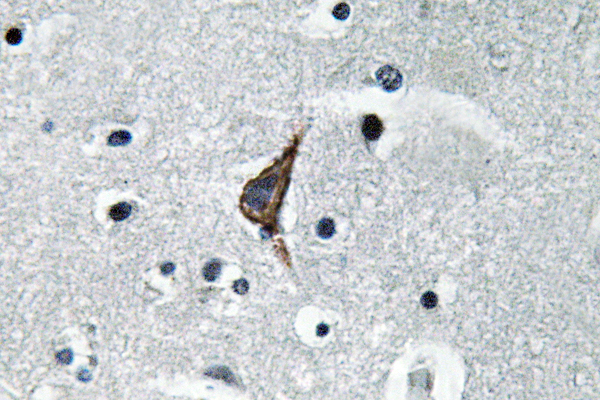

Immunohistochemistry analysis of TLR4 antibody in paraffin-embedded human brain tissue.

IHC 1:100-1:300;